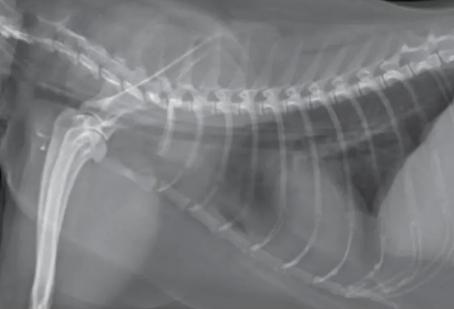

这种情况建议尽快就医且做影像学检查,

排除消化道站位性病变(瘤/癌)。